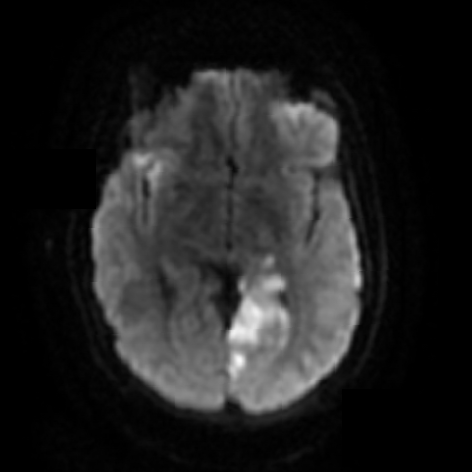

Cortical Strokes

• Most common finding (Cortically-based MCA strokes being the most common).

• Hemorrhagic conversion is common and complicates any use of anticoagulants/anti-thrombotics.